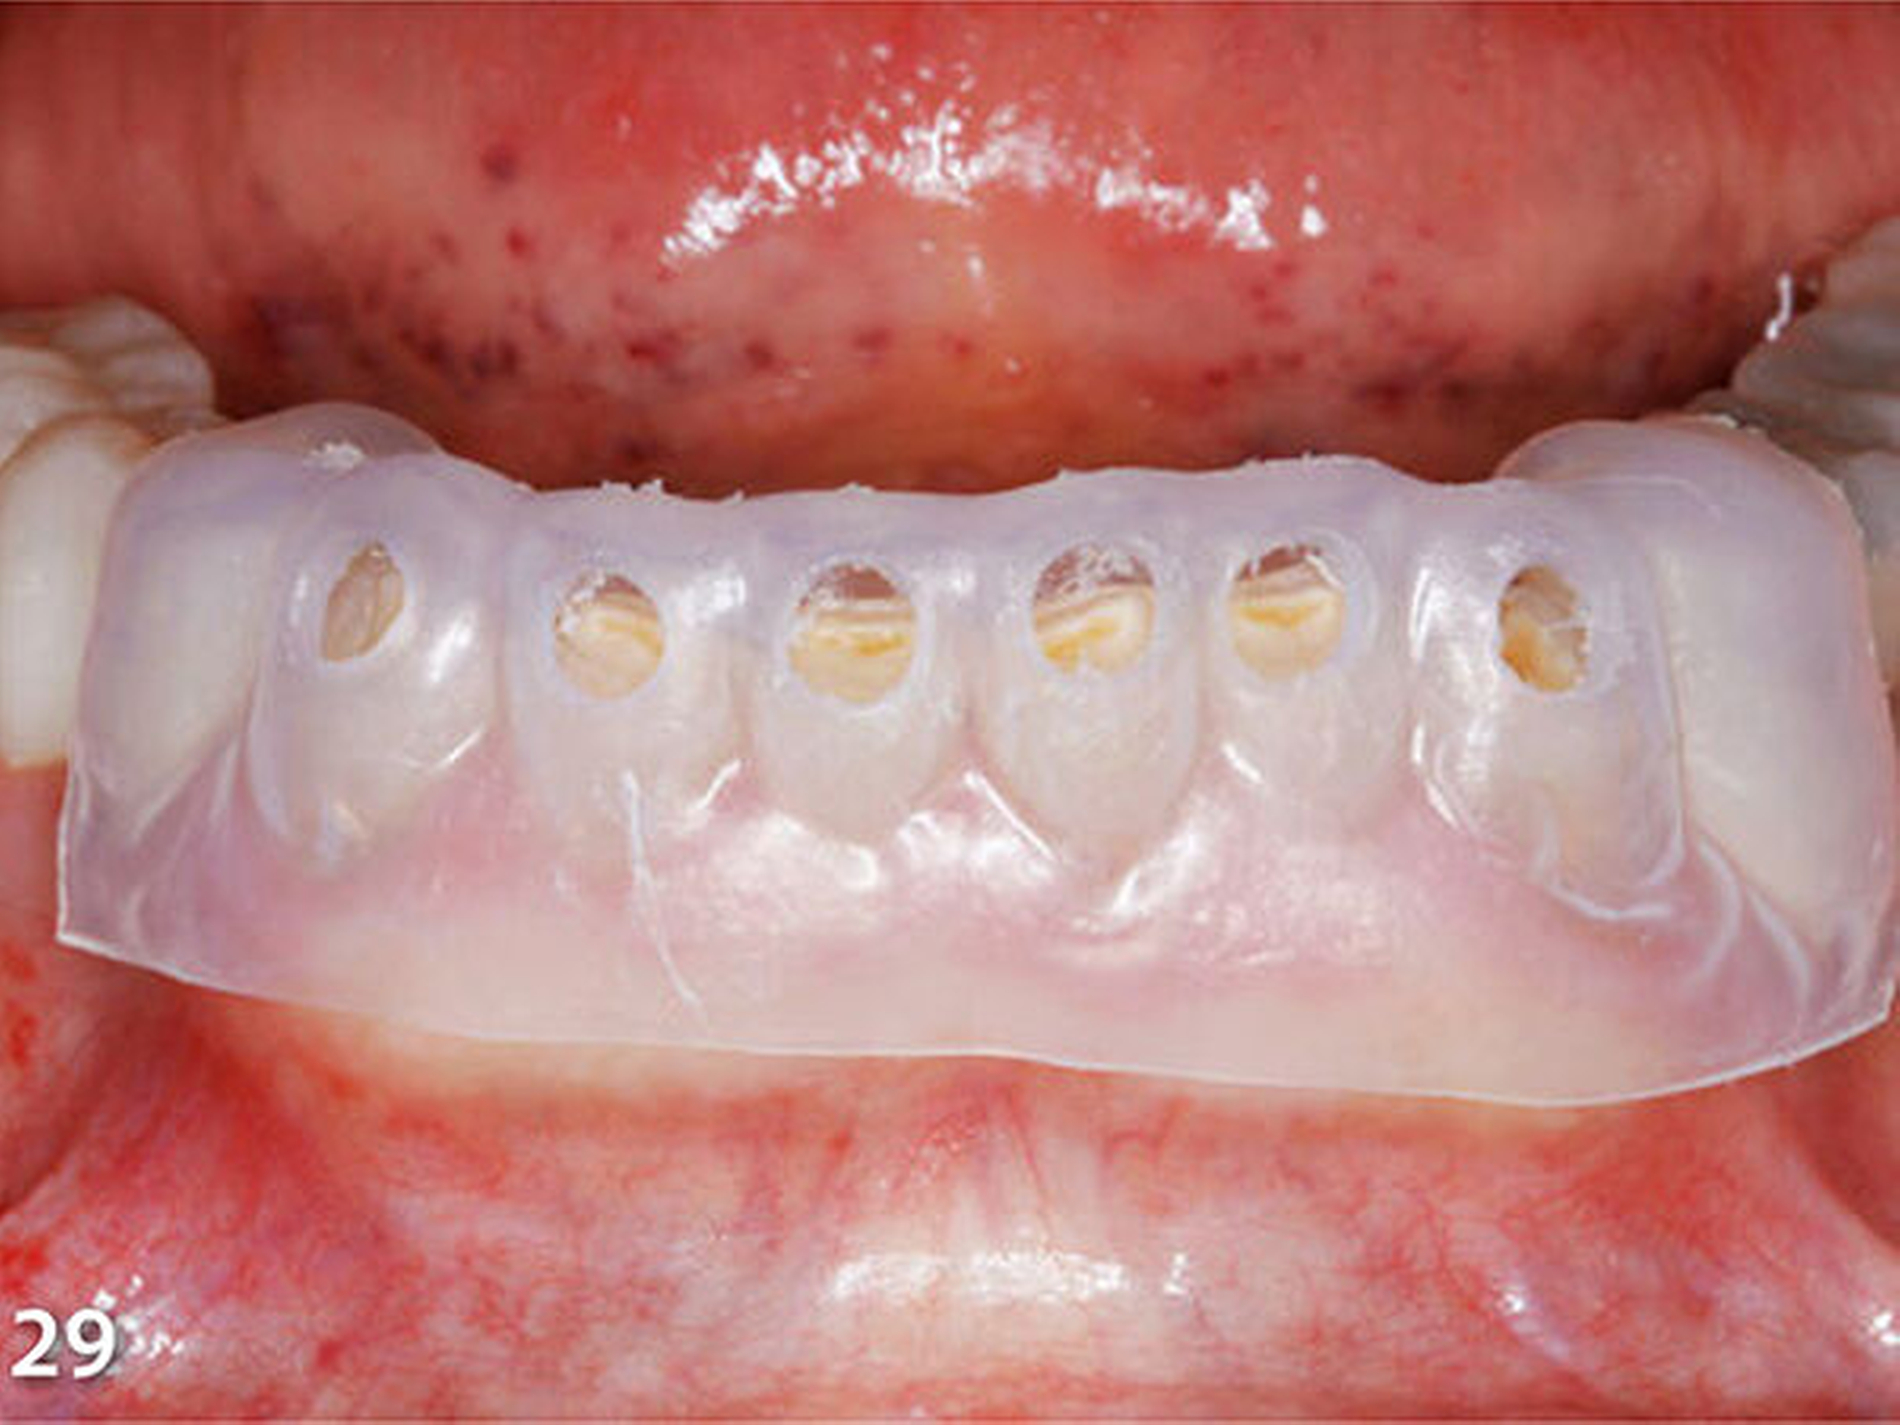

Analog erfolgte der Aufbau der Seitenzahnkauflächen der anderen Kieferhälfte ebenfalls in zwei Schritten (Abb.27). Durch den Aufbau aller Seitenzähne des Unterkiefers ist die temporäre Bisshebung bereits weitgehend abgeschlossen (Abb.28). Mit der dritten Übertragungsschiene (Schiene 3) (Abb.29) wurden die Unterkieferfrontzähne nach Ätzung der Zahnhartsubstanzen mit Phosphorsäure und nachfolgender adhäsiver Vorbehandlung inzisal aufgebaut (Abb.30).